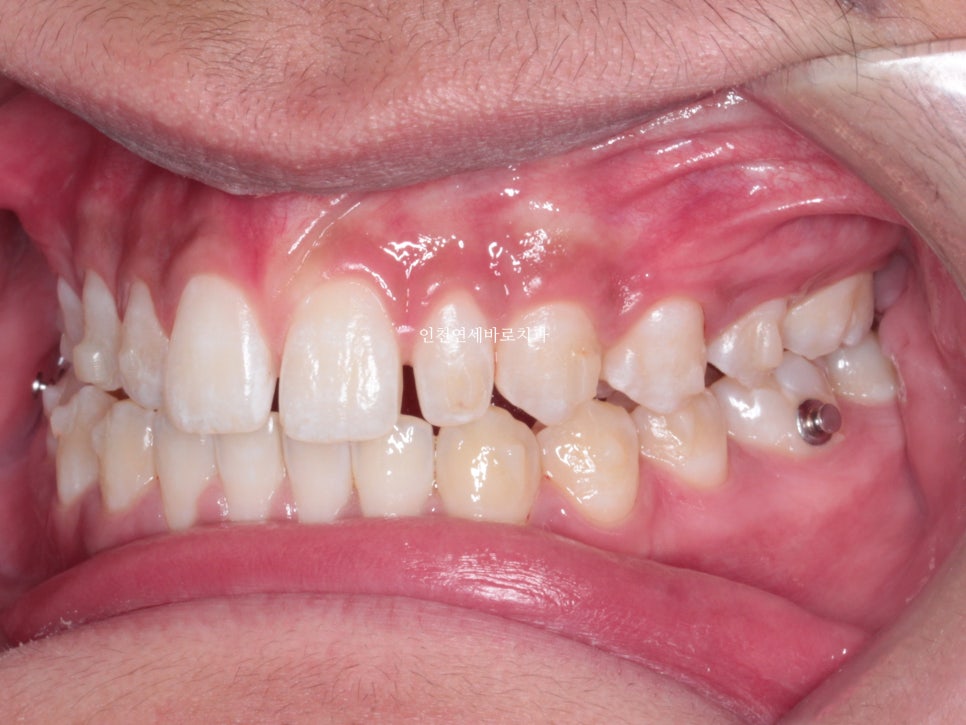

치료 받으러 온 고1 남학생입니다.

앞니가 벌어진 것도 문제였지만

화살표쪽에 보이는 반대교합도 문제였습니다.

인비절라인으로 치료를 하기로 했습니다.